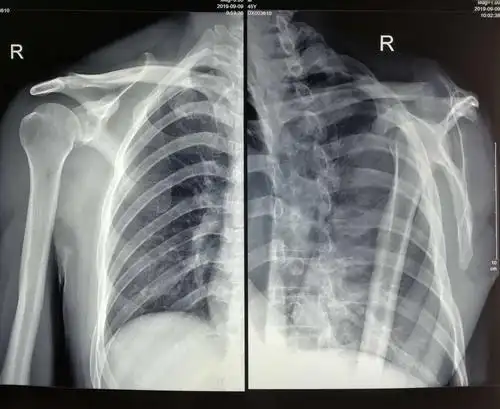

术后右肩关节正位片

术前左肩关节正位片提示:左肱骨大结节处骨赘形成(肩峰撞击引起)